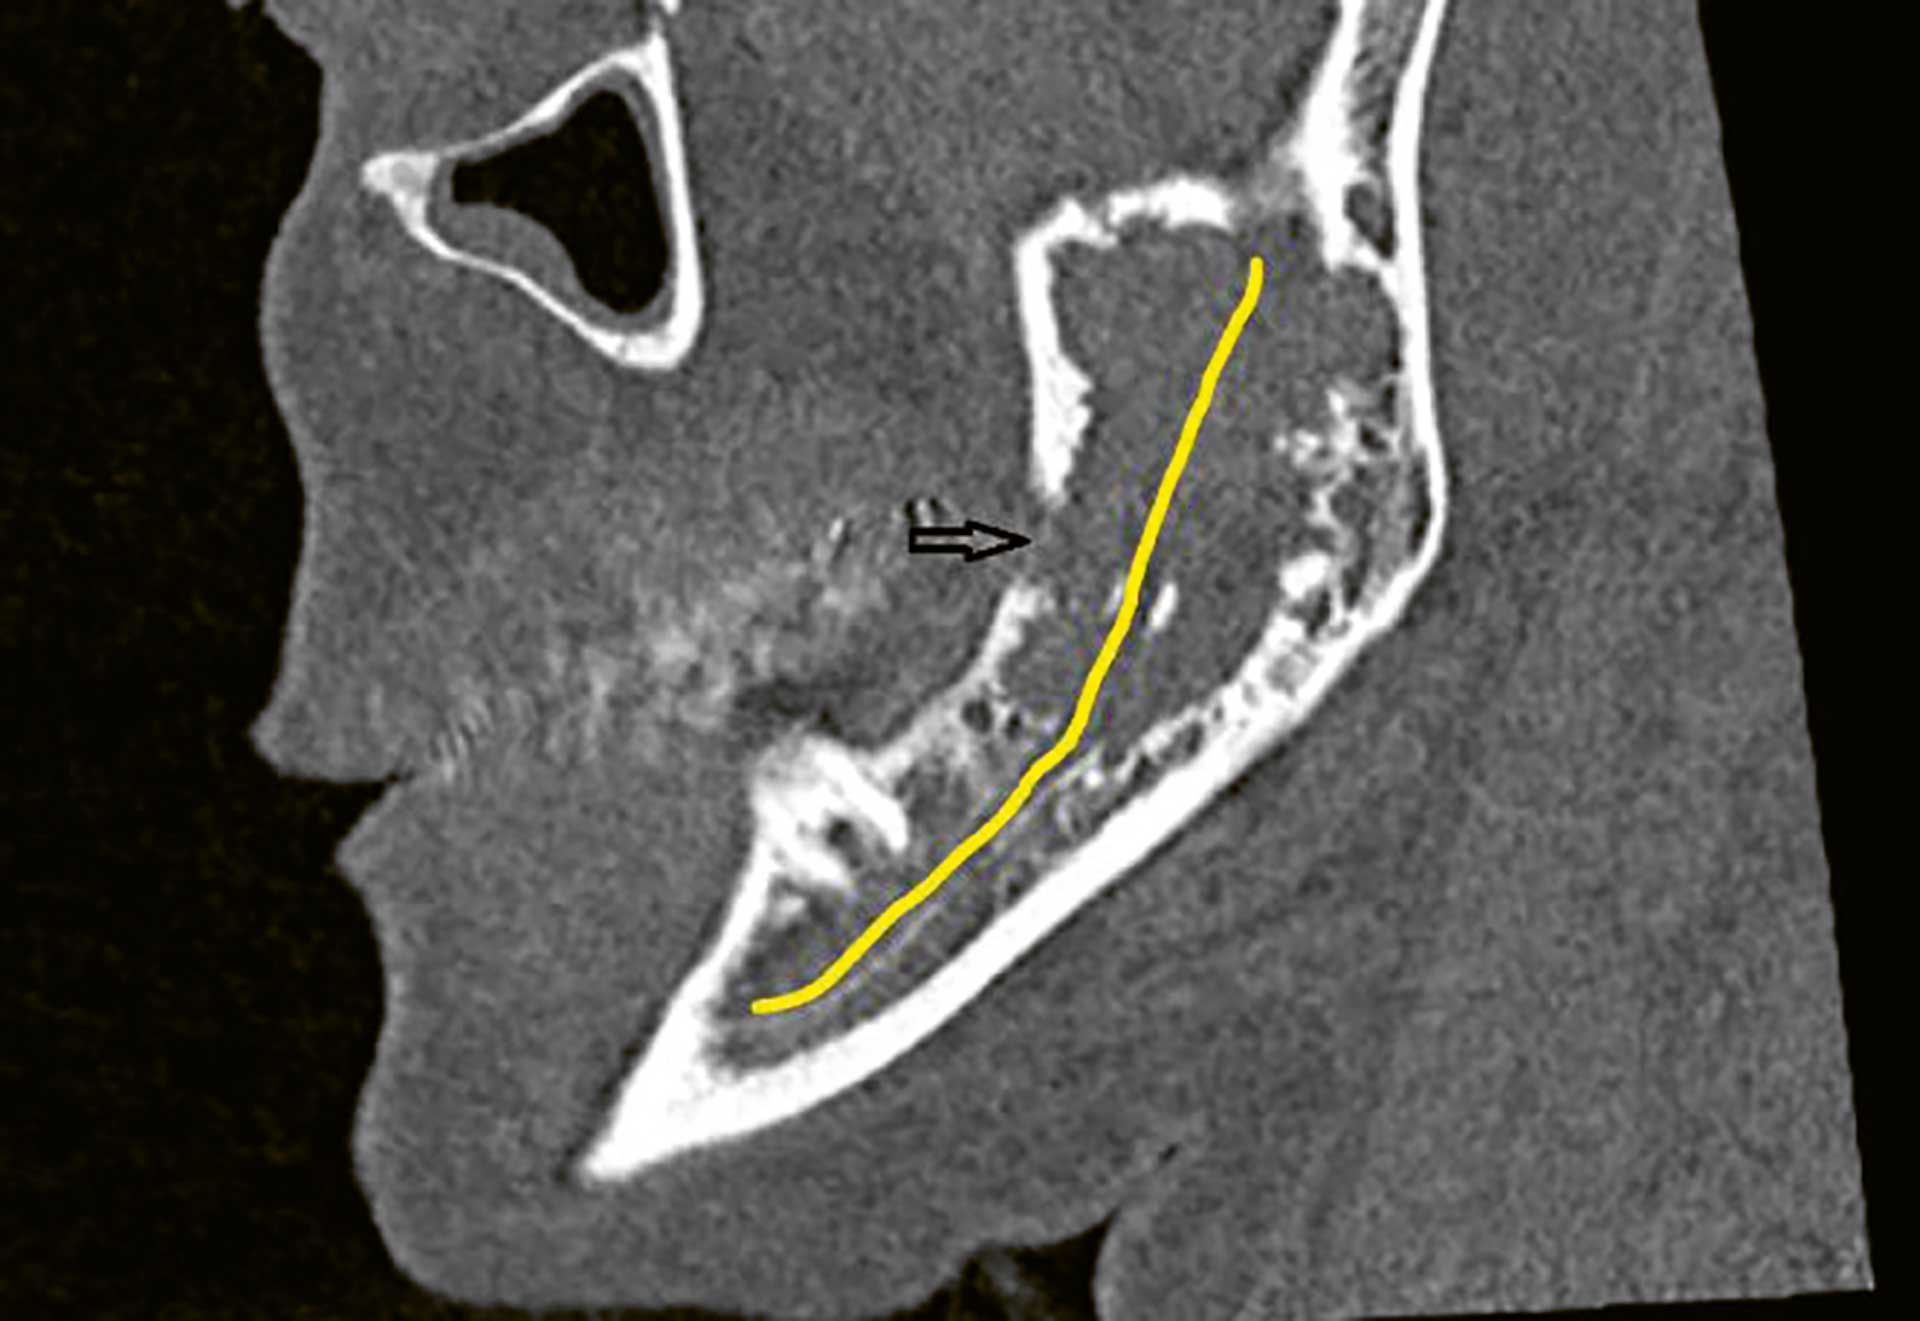

Figur 8 CT av ansiktsskjelettet viser breddeforøkt ramus og angulus, med manglende trabekulært bein i marghulen, og kortikal defekt (svart pil). Den gule linjen markerer nervekanalen/nervus alveolaris inferior.

CT viste en uregelmessig lytisk forandring som målte 25 x 10 x 40 mm. Flere områder viste kortikalt gjennombrudd, både medialt og lateralt. Ramus var breddeforøket, som ved ekspansiv vekst. Nervus alveolaris inferior forløp gjennom forandringen og var blottlagt uten synlig beindekning i store deler av forløpet.